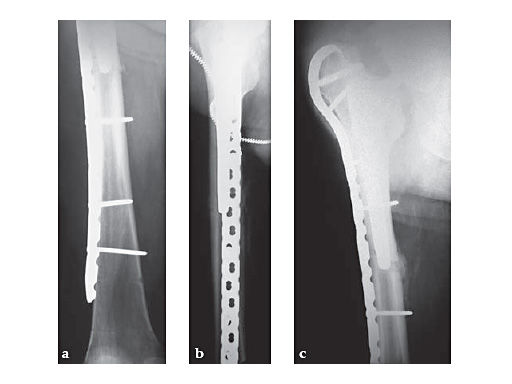

46-year-old female with an transverse intertrochanteric fracture

Case provided by Keith Mayo, Tacoma, USAHazards and labeling